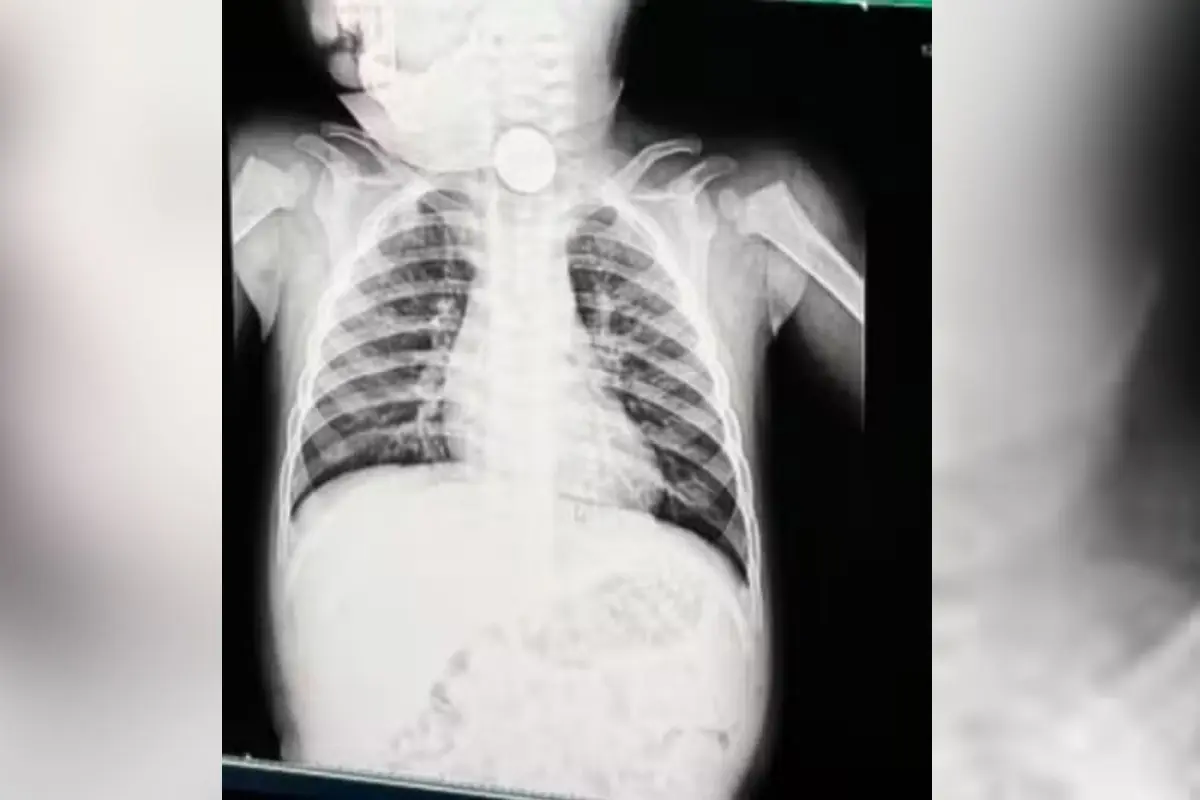

Exame revelou bateria do brinquedo lousa mágica no esôfago do bebê (Foto: redes sociais)

Pedro foi levado para atendimento médico, onde um exame de raio-x identificou um objeto no esôfago. Inicialmente, a suspeita era de que se tratava apenas de uma peça de algum brinquedo de plástico, o que fez com que o caso fosse tratado como menos urgente. Incomodados com a demora, os pais decidiram procurar outro serviço de saúde.

Após novos exames, os médicos confirmaram que o objeto era, na verdade, uma bateria tipo botão, semelhante às usadas em relógios. O item foi retirado por endoscopia depois de cerca de 12 horas no organismo da criança. Durante o procedimento, os profissionais identificaram sinais de necrose no esôfago e risco de perfuração, uma complicação grave que pode levar à infecção generalizada.